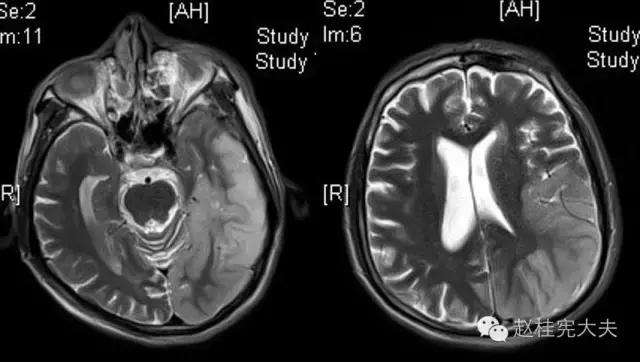

完善检查,头颅MRI回报:左侧颞顶枕叶急性梗死灶。

当看到磁共振片子的时候,我知道,我们忽略了一些东西......

患者的磁共振影像不符合脑血管病的血供分布,跨了大脑中动脉和大脑后动脉范围,且病灶偏皮层分布。大脑前、中、后动脉血供分布(横断面)见下图